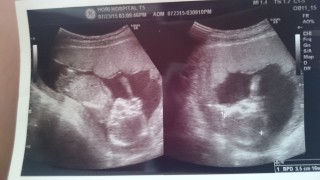

つわりもだいぶ落ち着いてきてからの妊婦検診2回目。前回の検診での検査の結果で何も問題なく一安心。背骨と脳と目がよくわかるエコー。性別はまた次回だね、と言われました。足を伸ばしてるらしいです。前回バタバタ動いていましたが、今回はおやすみ中かゆったり少しだけ動いていました。エコーでも問題なく、質問は?と聞かれ2週間後に飛行機に乗る予定があることを伝えたのですが、飛行機に乗ることで、赤ちゃんに何か問題が起こることはないでしょう、とのこと。保険証と母子手帳は携帯してください、と言われました。

腕をいっぱい振ってて可愛かった~